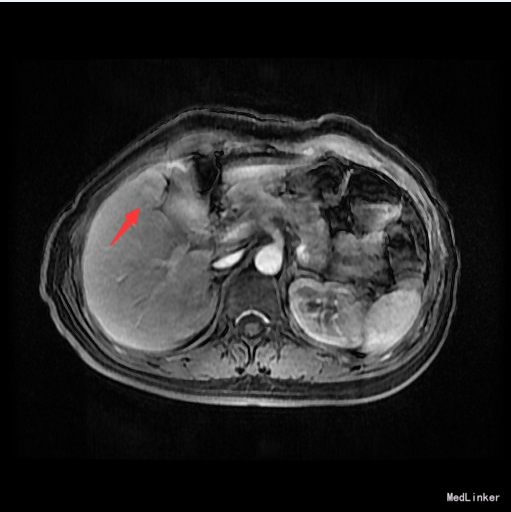

查体:腹平,腹壁静脉无显露,腹软,无压痛,无反跳痛。肝肋下未及。 辅查:AFP 3.43ng/ml, CEA 1.47ng/ml。MR:肝S5段占位性病变(26*25mm),考虑肝癌可能性大,建议活检。

随访:术后病理示:(右肝肿物)送检肝组织部分呈结节状增生,结节间见粗细不等的纤维间隔,其内见血管增生,少量淋巴细胞及浆细胞浸润,符合肝局灶性结节状增生(FNH)。 讨论:肝局灶性结节增生(FNH)是肝内第二常见良性肿瘤,一般无临床症状,影像学表现,MRI上T1WI和T2WI与周围肝实质信号相近,增强扫描动脉期明显强化,若存在中央瘢痕,则中央瘢痕不强化,门脉期及静脉期强化程度减退,中央瘢痕则呈延迟强化。FNH需与肝癌和肝腺瘤鉴别,本例即误诊为肝癌,若存在中央瘢痕,则诊断较容易。